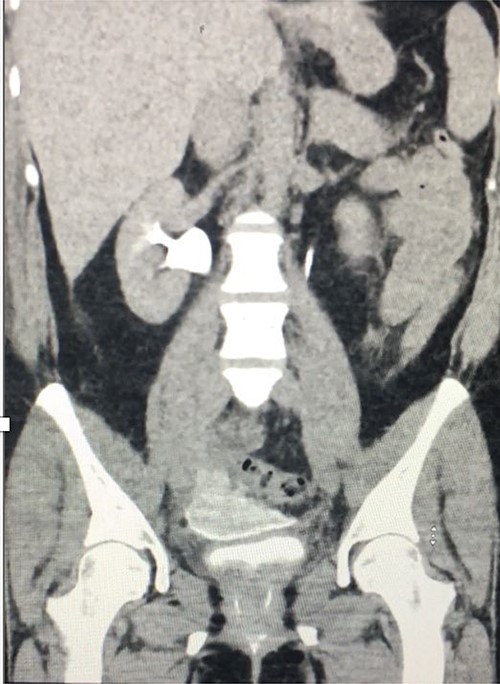

Computed tomography (CT) with urographic phase imaging demonstrated a right distal ureteric injury with leakage of urine into the pelvis and fistulation into the vagina (Figs 1 and 2). A diverting right percutaneous nephrostomy was inserted in the interventional radiology (IR) suite. An antegrade ureterogram at the same time demonstrated a complete discontinuation of the ureter which appeared retracted (Fig. 3).

Coronal nephrogenic phase CT urogram showing hydronephrosis of the right renal pelvis.